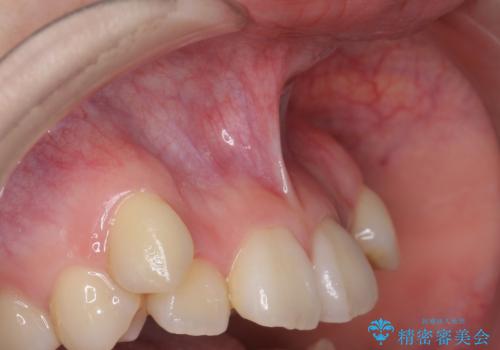

[滑舌が気になる] 舌小帯形成術

担当医 大元洋佑

![[滑舌が気になる] 舌小帯形成術の症例 治療前](https://seimitsushinbi.jp/wp/wp-content/uploads/2020/04/8ed6139f5e3748a3a4e75c04a8849f3e-500x350.jpg?v=1587871433)

![[滑舌が気になる] 舌小帯形成術の症例 治療後](https://seimitsushinbi.jp/wp/wp-content/uploads/2020/04/fb799f9ba89416b633853e7babc41469-500x350.jpg?v=1587871469)